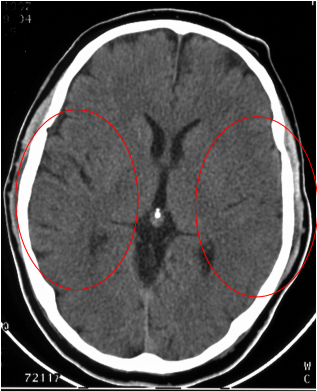

TDM (Scanner) Cérébral: L’Ischémie apparait comme une hypodensité spontannée (noire ou sombre) dans le territoire vasculaire atteint

- AVCI sylvien superficiel:

On peut également avoir des signes indirects avant 48h au scanner (effacement des sillons corticaux,trop belle artère sylvienne):